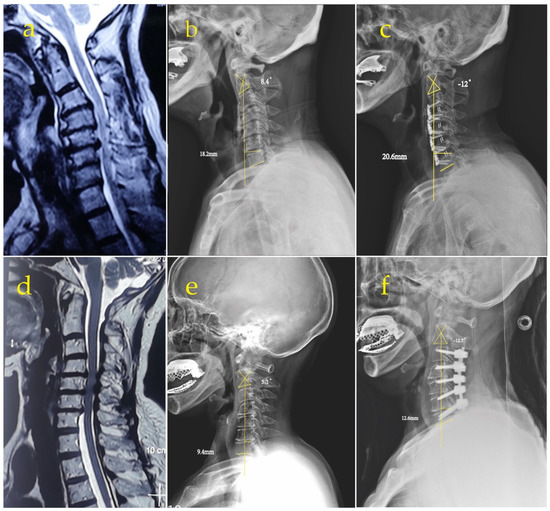

The Efficacy of Cervical Lordosis Rehabilitation for Nerve Root Function and Pain in Cervical Spondylotic Radiculopathy: A Randomized Trial with 2-Year Follow-Up

Sagittal cervical alignment is a clinically related feature in patients suffering from chronic cervical spondylotic radiculopathy (CSR). We designed this randomized trial to explore the effects of cervical lordosis (CL) correction in thirty chronic lower CSR patients with CL < 20°. Patients were [...] Read more.

Sagittal cervical alignment is a clinically related feature in patients suffering from chronic cervical spondylotic radiculopathy (CSR). We designed this randomized trial to explore the effects of cervical lordosis (CL) correction in thirty chronic lower CSR patients with CL < 20°. Patients were assigned randomly into two equal groups, study (SG) and control (CG). Both groups received neck stretching and exercises and infrared radiation; additionally, the SG received cervical extension traction. Treatments were applied 3× per week for 10 weeks after which groups were followed for 3 months and 2 years. The amplitude of dermatomal somatosensory evoked potentials (DSSEPS), CL C2–C7, and pain scales (NRS) were measured. The SG had an increase in CL post-treatment (p < 0.0001), this was maintained at 3 months and 2 years. No statistical improvement in CL was found for the CG. A significant reduction in NRS for SG after 10 weeks of treatment with non-significant loss of change at 3 months and continued improvement at 2 years was found. CG had less significant improvement in post-treatment NRS; the 3-month and 2-year measures revealed significant worsening in NRS. An inverse linear correlation between increased CL and NRS was found (r = −0.49; p = 0.005) for both groups initially and maintained in SG at the final 2-year follow-up (r = −0.6; p = 0.01). At 10 weeks, we found significant improvements in DSSEPS for both groups (p < 0.0001). We identified a linear correlation between initial DSSEPs and CL for both groups (p < 0.0001), maintained only in the SG at the final follow-up for all levels (p < 0.0001). Improved CL in the SG correlated with significant improvements in nerve root function and pain rating in patients with CSR at short and long-term follow-up. These observed effects indicate that clinicians involved in the treatment of patients with symptoms of cervical degenerative disorders should add sagittal curve correction to their armamentarium of rehabilitation procedures for relevant patient populations. Full article